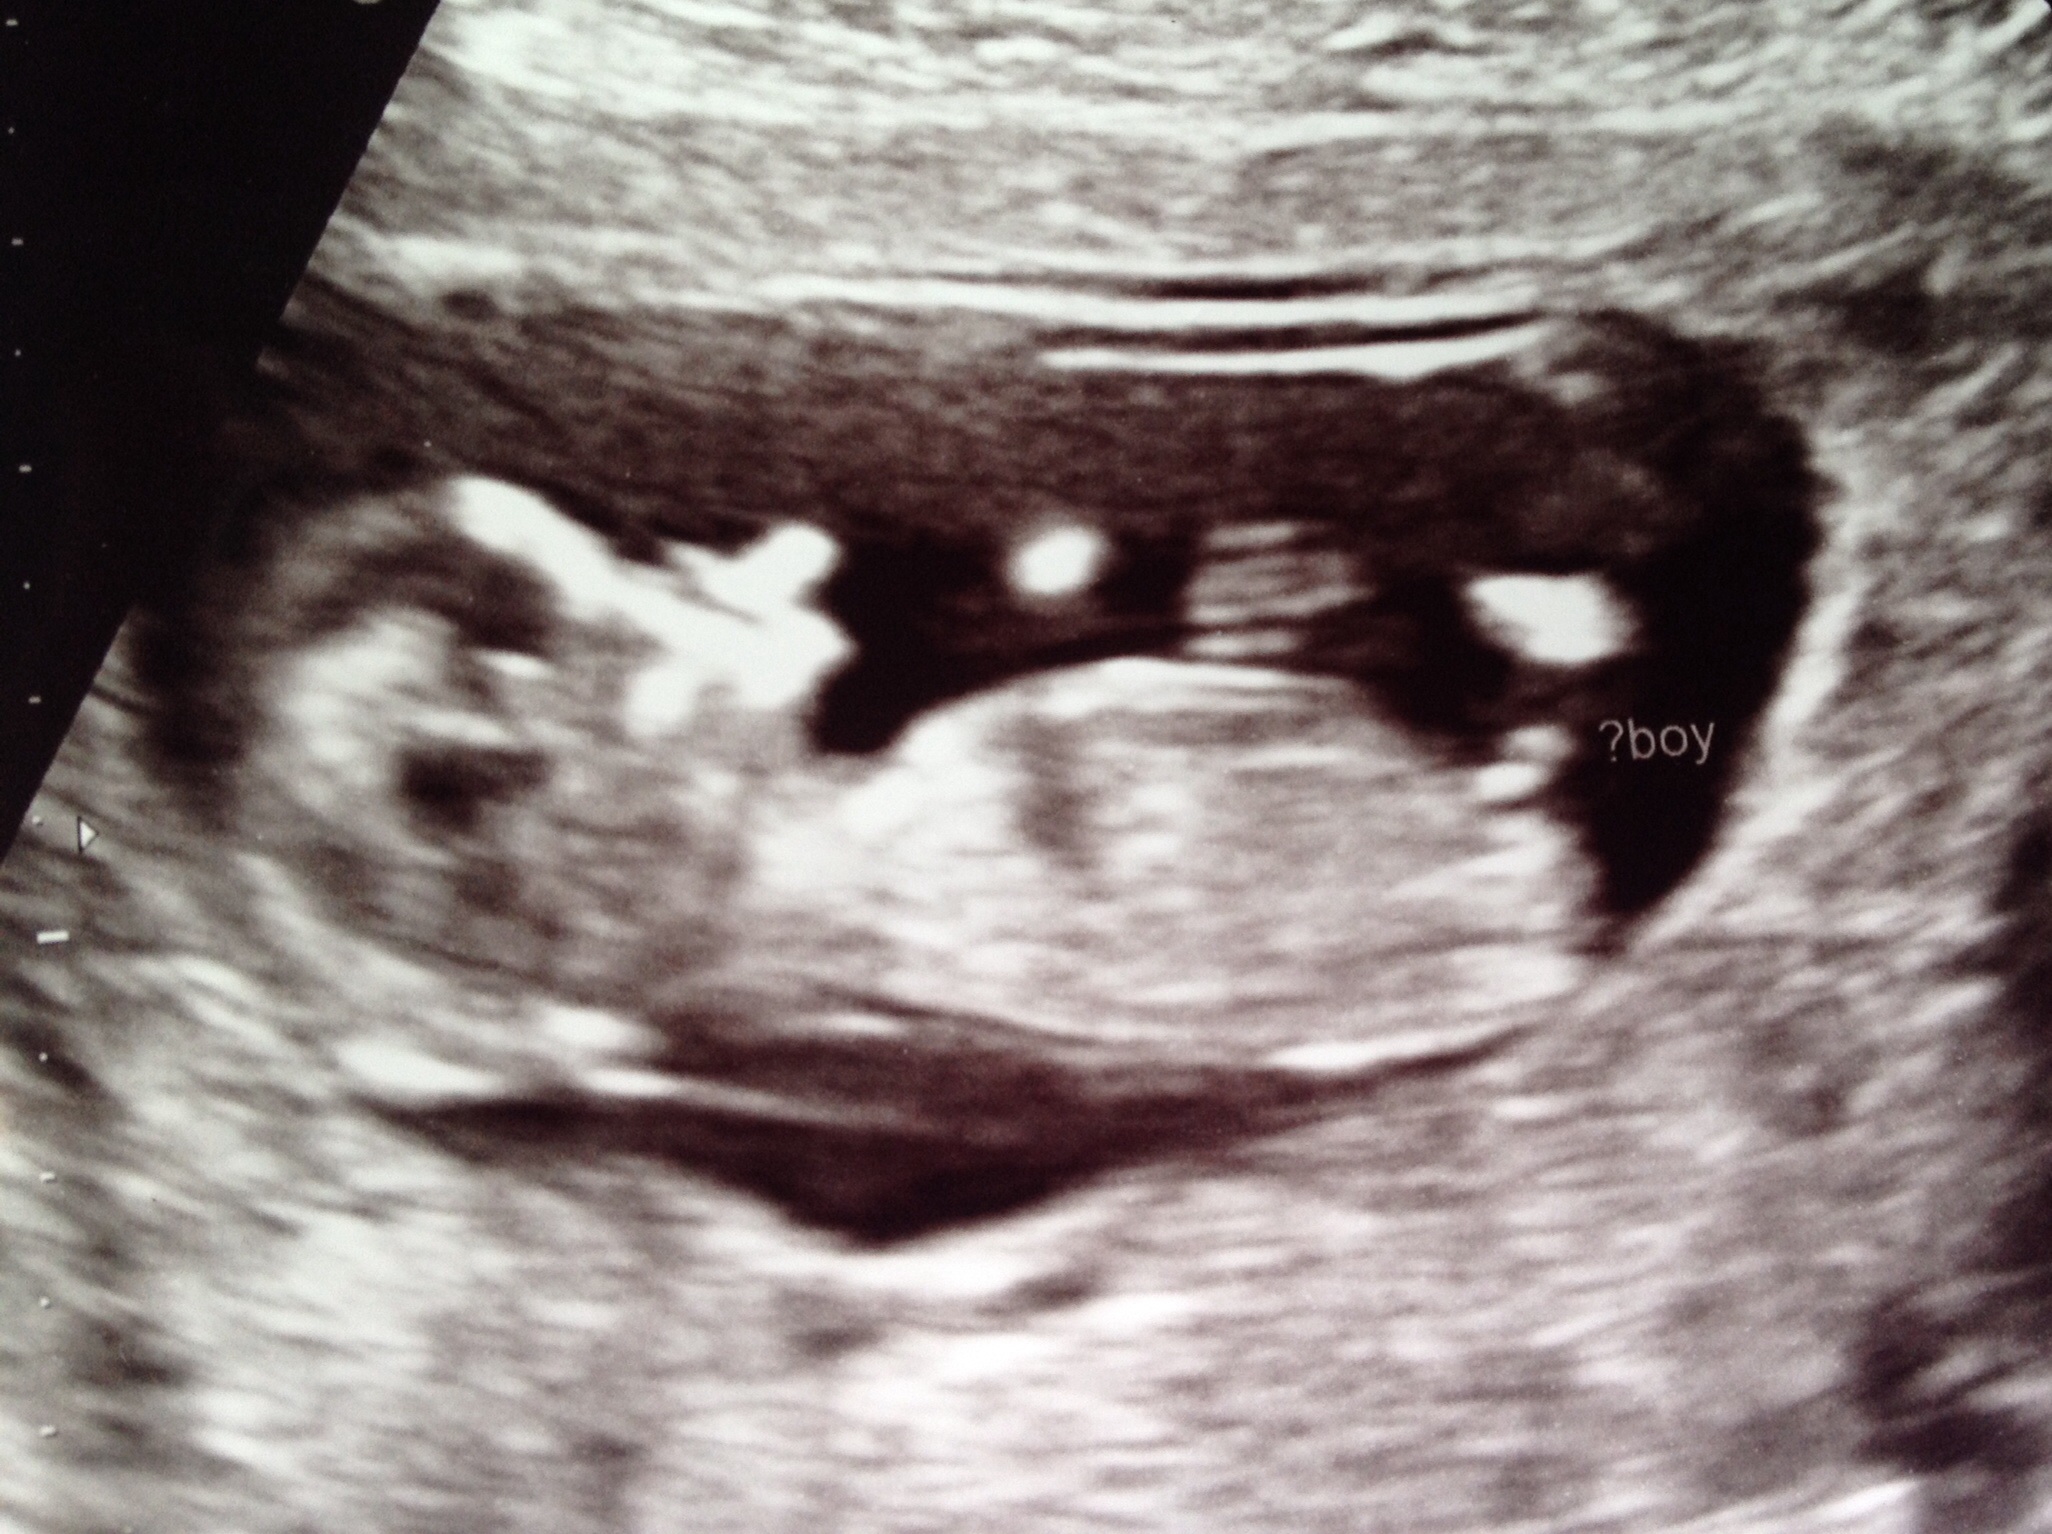

Had a scan today at 11 weeks 5 day (NT scan). Tech guessed boy but said she wasn't sure, maybe 60 percent. Any guesses? This will be our third blue baby if so!Attachment 18772

Looks like a clear boy nub. Congrats!

Very boyish nub, I would be surprised if it turned out to be a girl. Congratulations on a baby boy x

That is a boy nub, especially that early on, but anything can happen. I have seen some classic boy nubs turn out to be girls. Remember these are all guesses based on a theory.